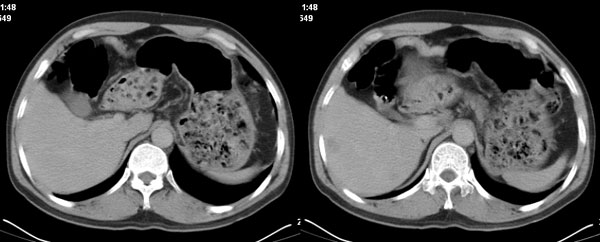

李**,男,46岁,便血1天入院,慢性贫血貌,腹平、软,剑突下压痛,肠鸣音稍活跃,hb大于1g/l,胃镜:慢性浅表性胃炎,b超:1肝内多发性占位 2腹腔内囊性肿块 ,肝内圆形影平扫ct值42.9,动脉期48.6,静脉期58.2,延迟期62.2

影像学表现:1 腹腔前中部、胰腺前方囊实性病灶(个人认为确定有否实性成分存在这是关键,涉及到鉴别诊断,如果是口服阳性造影剂则可明确左侧是不是小肠了),囊性部分囊壁不均,实性部分有强化,与小肠关系较密切,局部小肠受推移;与胰头、胃后壁均有脂肪间隙存在;2 胰腺无异常改变,胰周无渗出;3肝后段包膜下2个小圆形低密度灶,从图像和楼主提供的ct值来看有轻度强化,灶周无片状强化,不似单纯囊肿及肝癌、炎性病变表现;4 腹膜后及腹腔内无淋巴结肿大。

胰腺边界清晰,胰周筋膜不厚,胰周脂肪密度无明显增高;其前方囊实性病灶,边界清晰,增强后实性部分轻度强化;肝内多发边界清晰低密度影,增强后无明显强化(平扫ct值42.9,动脉期48.6,静脉期58.2,延迟期62.2)。

我们先确定病变来源于何处。从片上看,应该说是起源于肠道的囊实性的肿块。二、肝内低密度影,增强强化随时间强化,考虑小血管瘤。